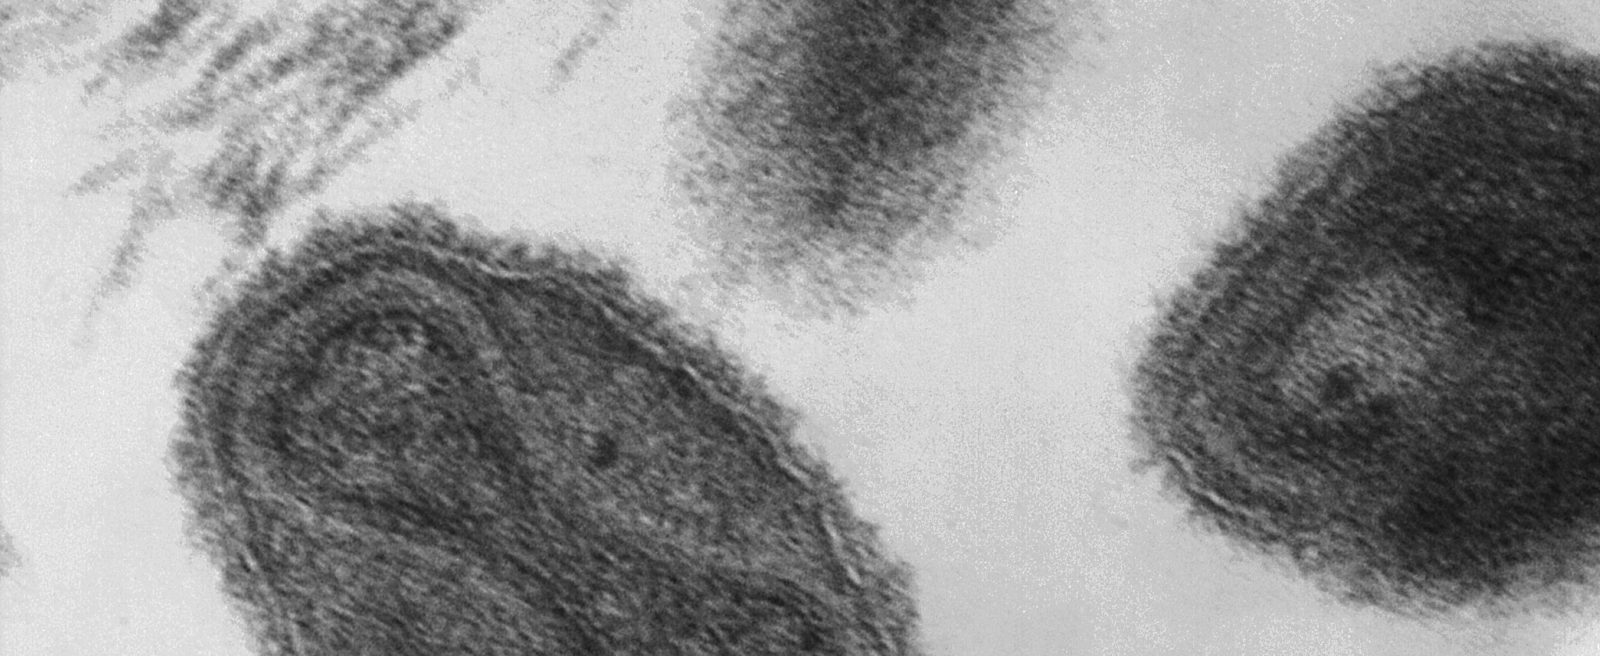

Virus de la viruela (Viruela). Dentro del virión podemos ver una especie de estructura con forma de mancuerna, se trata del material genético del virus, que es ADN. En la imagen podemos ver una micrografía al microscopio electrónico de transmisión (TEM) a 370.000 aumentos.